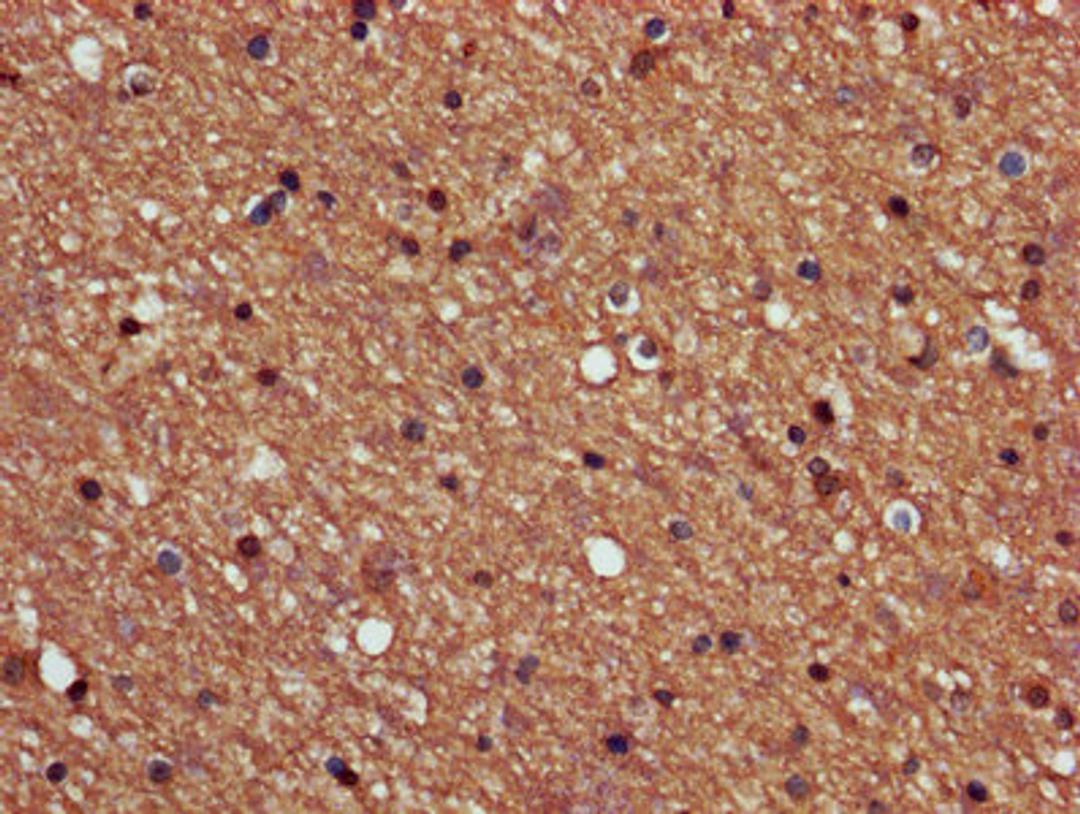

IHC image of CSB-PA018565LA01HU diluted at 1:600 and staining in paraffin-embedded human brain tissue performed on a Leica BondTM system. After dewaxing and hydration, antigen retrieval was mediated by high pressure in a citrate buffer (pH 6.0). Section was blocked with 10% normal goat serum 30min at RT. Then primary antibody (1% BSA) was incubated at 4°C overnight. The primary is detected by a biotinylated secondary antibody and visualized using an HRP conjugated SP system.